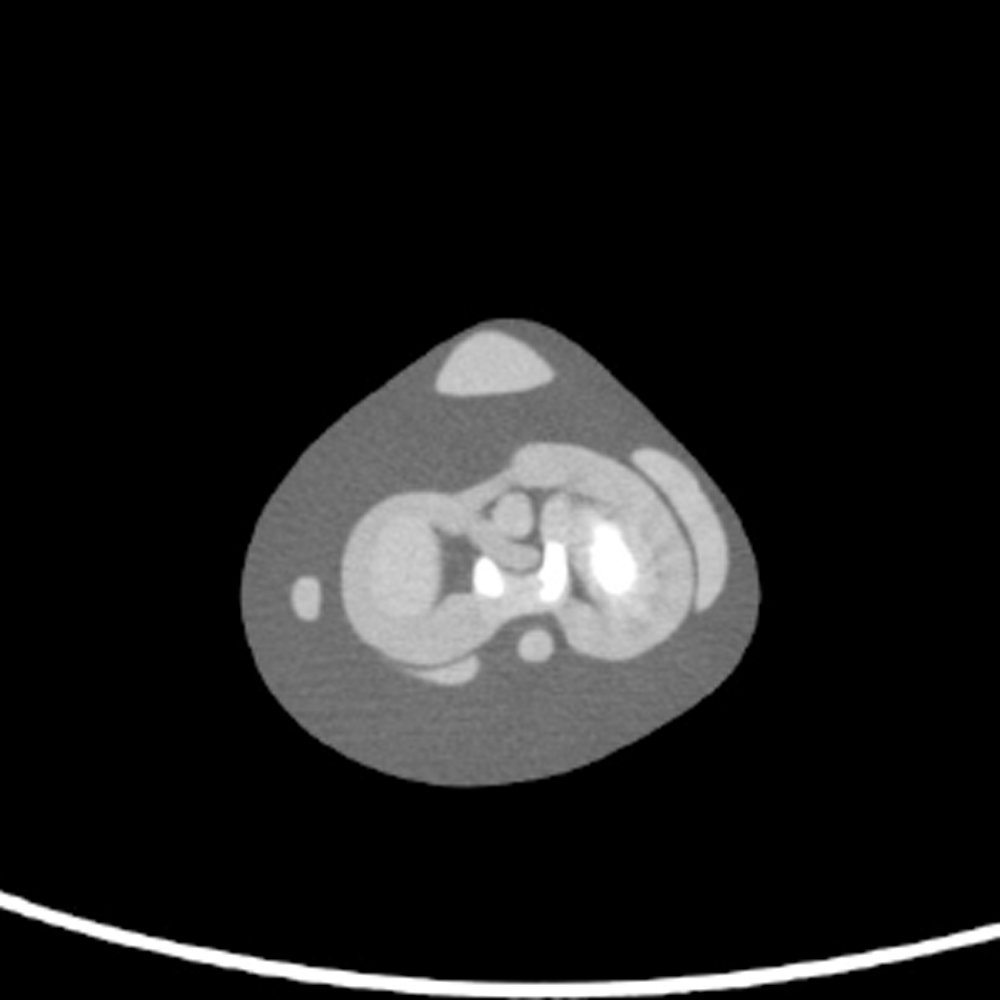

Detailed knee anatomy with HU of each bone, cartilage, and ligament

- Knee Phantom

PH-71

| Features | 1. Anthropomorphic knee phantom that allows visualization of ligaments and cartilage / 2. Close-to-human radiation absorption and HU for each anatomical structure |

| Anatomy | femur / tibia / fibula / patella / articular cartilage of patella / meniscus / cruciate ligament / medial collateral ligament / fibular |